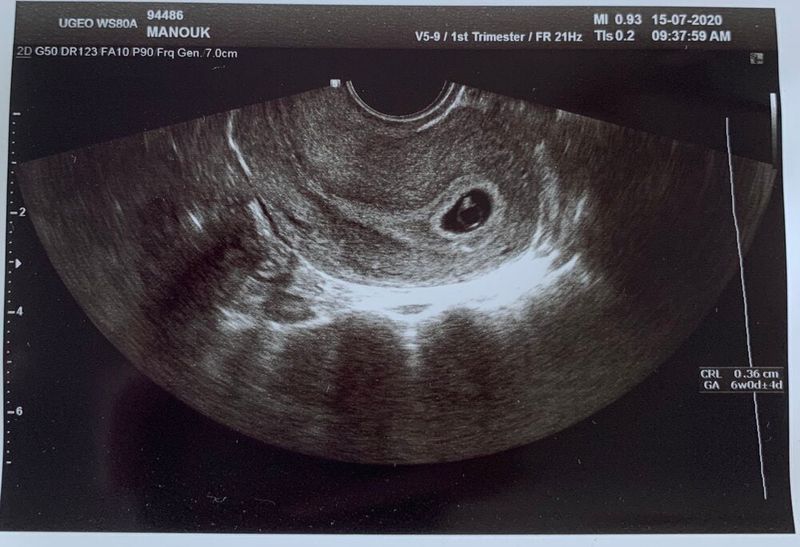

We proberen veel afleiding te zoeken in de dagen die volgen. Elke dag plannen we iets, om op die manier maar gewoon bezig te zijn. Mijn gedachten en gevoelens gaan heen en weer. Ik ben gefocust op alles wat ik voel en vooral niet voel. Ik Google me suf (al had ik me voorgenomen dat niet te gaan doen). Naarmate de dagen voorbij gaan, wordt het spannender en spannender, totdat het eindelijk de dag is dat ik mag laten bloedprikken. Koen werkt weer vanaf kantoor, dus hij zal er dit keer niet bij zijn wanneer ze me gaan bellen met de uitslag. Ik merk dat ik dat wel jammer vind, maar goed, het is niet anders. Rond de middag gaat mijn telefoon en ik zie dat de kliniek belt. Mijn hart slaat een paar keer over, ik zucht een paar keer heel diep en neem de telefoon op. Gelukkig laat de verpleegkundige me niet lang wachten en vertelt me dat ik zwanger ben. Ik val om van verbazing, want die zag ik echt niet aankomen. Ik was ervanuit gegaan dat het niks zou worden. Maar jongens, ik ben gewoon zwanger! De komende weken zal ik meerdere keren bloed moeten laten prikken om te kijken of het HCG-hormoon goed oploopt. Als dat zo is, zal er een eerste echo ingepland gaan worden. De weken die volgen zijn spannend. Om de zoveel dagen moet ik naar de kliniek voor een bloedonderzoek. Elke keer word ik gebeld met een goede uitslag. Ik kan het haast niet geloven en stroom over van geluk. Op 15 juli is het eindelijk zo ver: de eerste echo staat gepland. Het voelt goed, maar toch ben ik rete-zenuwachtig. Koen gaat met me mee en gelukkig zijn we al snel aan de beurt. De arts vraagt hoe ik me voel en zegt daarna al snel dat we gaan kijken. Vrijwel meteen zie ik het, een grijzige vlek met een wit knipperend stipje. Er zit gewoon een kindje in mijn buik, met hartslag! Ik kan wel janken van geluk. Er is gewoon één embryo blijven plakken. Ik ben gewoon echt zwanger. Na al die jaren van ellende en verdriet, zou het dan echt eindelijk gelukt zijn?! De arts zegt dat alles er perfect uitziet voor dit termijn. Ik ben begin maart uitgerekend en de komende weken zal er elke twee weken een echo gepland worden om in de gaten te houden hoe alles loopt. Wanneer Koen en ik in de auto stappen, rollen de tranen over mijn wangen. Ik ben zó intens gelukkig en dankbaar. Gaan we eindelijk papa en mama worden?!